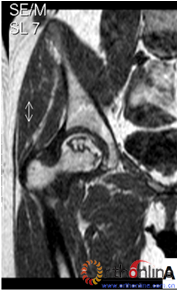

2. 依据SARS后ARCO分期Ⅰ期的ONFH患者(自然进展组)初次普查时的MRI或CT片,选用冠状位正中层面的T1WI(MRI)图像或冠状位二维重建的正中层面的(CT)图像,根据坏死灶占据外侧柱情况分为三型。Ⅰ型:坏死灶占据中央及内侧柱,外侧柱完全保留;Ⅱ型:部分外侧柱被坏死灶占据,部分保留(至少外侧皮质保留);Ⅲ型:坏死带穿透股骨头骨髓与外侧皮质,外侧柱无存留。(图2)

图2-1

图2-2

图2-3

图2 依据股骨头外侧柱存留情况,股骨头坏死的分型。(图2-1)分为Ⅰ型(外侧柱全部存留)(A)MRI图像显示;(B)7年后CT显示股骨头仍未塌陷;(图2-2)Ⅱ型(外侧柱部分保留)(A)MRI显示外侧皮质存留;(B)4年后CT显示股骨头仍未塌陷;(图2-3)Ⅲ型(坏死带穿透股骨头);(A)MRI显示坏死带;(B)2年后股骨头塌陷

Fig 2 According to preservation of the lateral pillar, the necrosis was divided into three types. (Fig 2-1)Type Ⅰ: Whole lateral pillar preserved (A) MRI showing; (B) no collapse occurred seven years later by CT showing. (Fig 2-2)Type Ⅱ: Preservation of the partial lateral pillar, (A) MRI showed the preservation of the lateral cortical bone; (B) no collapse of the femoral head four years by CT. (Fig 2-3)Type Ⅲ: the necrotic line pass through the cortical bone and bone morrow ;(A) MRI showed the necrotic line; (B) collapse of the femoral head occurred two year later.